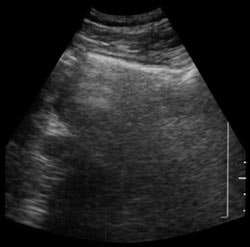

| Shadowing from bowel gas prevents visualization of pancreatic carcinoma (left). Following administration of SonoRx, a large hypoechoic mass is seen in the head of the pancreas (right). Images courtesy of Bracco Diagnostics. | |

Twenty-five patients with suspected pancreatic pathology underwent ultrasonography before and after ingesting 400 ml of SonoRx, a simethicone-coated cellulose oral contrast agent manufactured by Bracco Diagnostics of Princeton, NJ. The agent works by absorbing and dispersing gas bubbles in the stomach, thus reducing shadow artifacts.